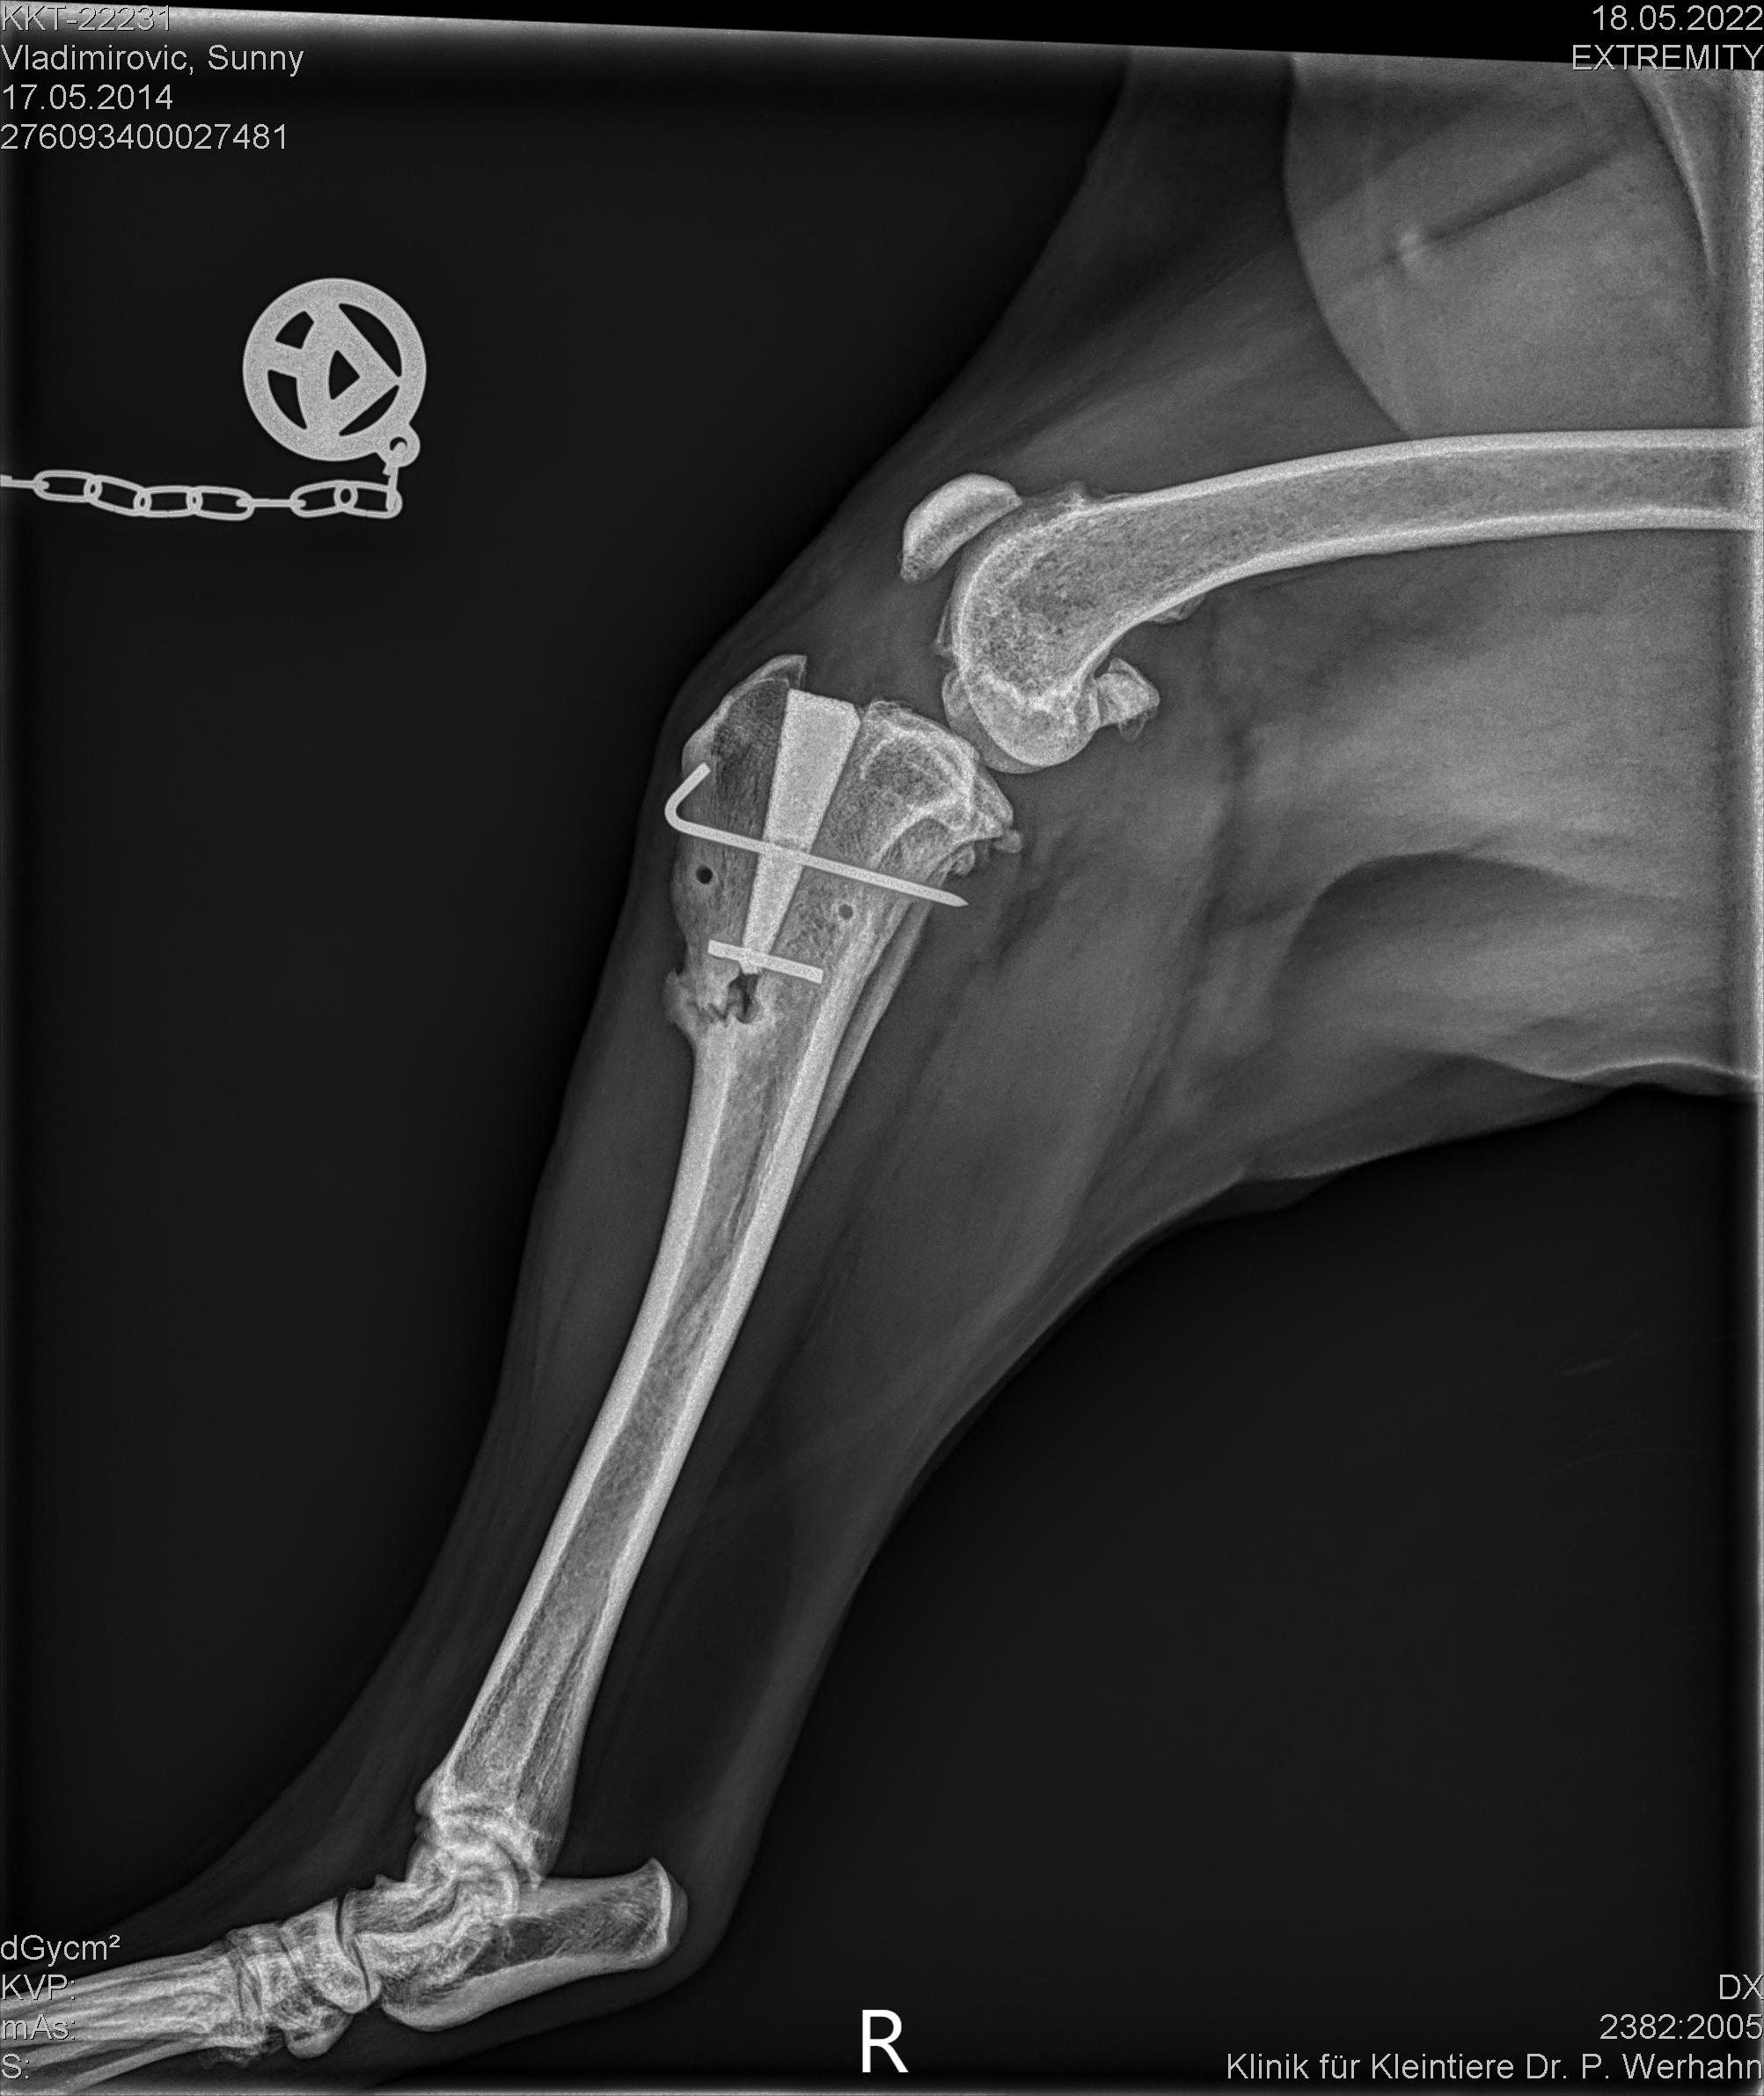

Mal ein Update...Nachdem wir in der 5. Woche nach OP durch Röntgen erfuhren, dass ihr Knochen genau unterhalb des eingesetzten Keils an der Schwachstelle gebrochen war, waren wir erstmal etwas entsetzt. Aber es war deutliche Kallusbildung zu sehen, was bedeutet, dass der Bruch ja schon ganz am Anfang passiert sein muss, als sie noch den Stützverband trug, der genau das verhindern sollte, und wo sie sowas von lieb war und keine Treppe stieg, oder zu schnell lief, also wie auch immer...... Aber es erklärte das humpeln nach relativ wenig Belastung und vor allem nach dem 3 Min. Schwimmen, was wir in Absprache mit der Therapeutin damals gerade gewagt hatten. Der Keil saß aber fest, das ist die Hauptsache. Nun gut, also weiter Physio und langsam steigende Belastung. Sie ist ein wirklich wunderbarer Patient. Jetzt in der 10. Woche hat sie es satt, will endlich wieder normal toben und rennen, da müssen wir sie noch bremsen. Sie ist aber schlau, wenn sie anfängt zu rennen belastet sie das Bein weniger....Sie schafft wieder 2 km Spaziergang und heute haben wir es wieder gewagt und waren mit ihr schwimmen. Also Wassertherapie, da dort auch Wassertreten gut möglich ist

Der Bruch ist an der Stelle wohl sehr häufig, da der Knochen sehr dünn ist da und nur durch die Knochenhaut gehalten wird. Ist nicht so schlimm meinte die Therapeutin.

Auf dem Bild seht ihr es, die Beule davor ist die Kallusbildung. Soll sich zurückbilden meinte sie. Bin auf das Röntgenbild in 3 Wochen oder so gespannt. Unter dem Keil ist ein Bohrloch und von da geht der Bruch. Nein Stützverband hatte sie nur die ersten 2 Wochen, seitdem nix mehr. Hatte halt nur die weisung wieviel bewegung, keine treppen, kein springen, kein toben, langsam gehen. Und Bewegungsübungen. Die Narbe sah scheußlich aus nach Fäden ziehen, total wulstig und so. Sollte da massieren, fand sie nicht gut. Hab stattdessen dmso und beinwellsalbe raufgemacht. Nach einer Woche wahr die Narbe vollkommen glatt und schön